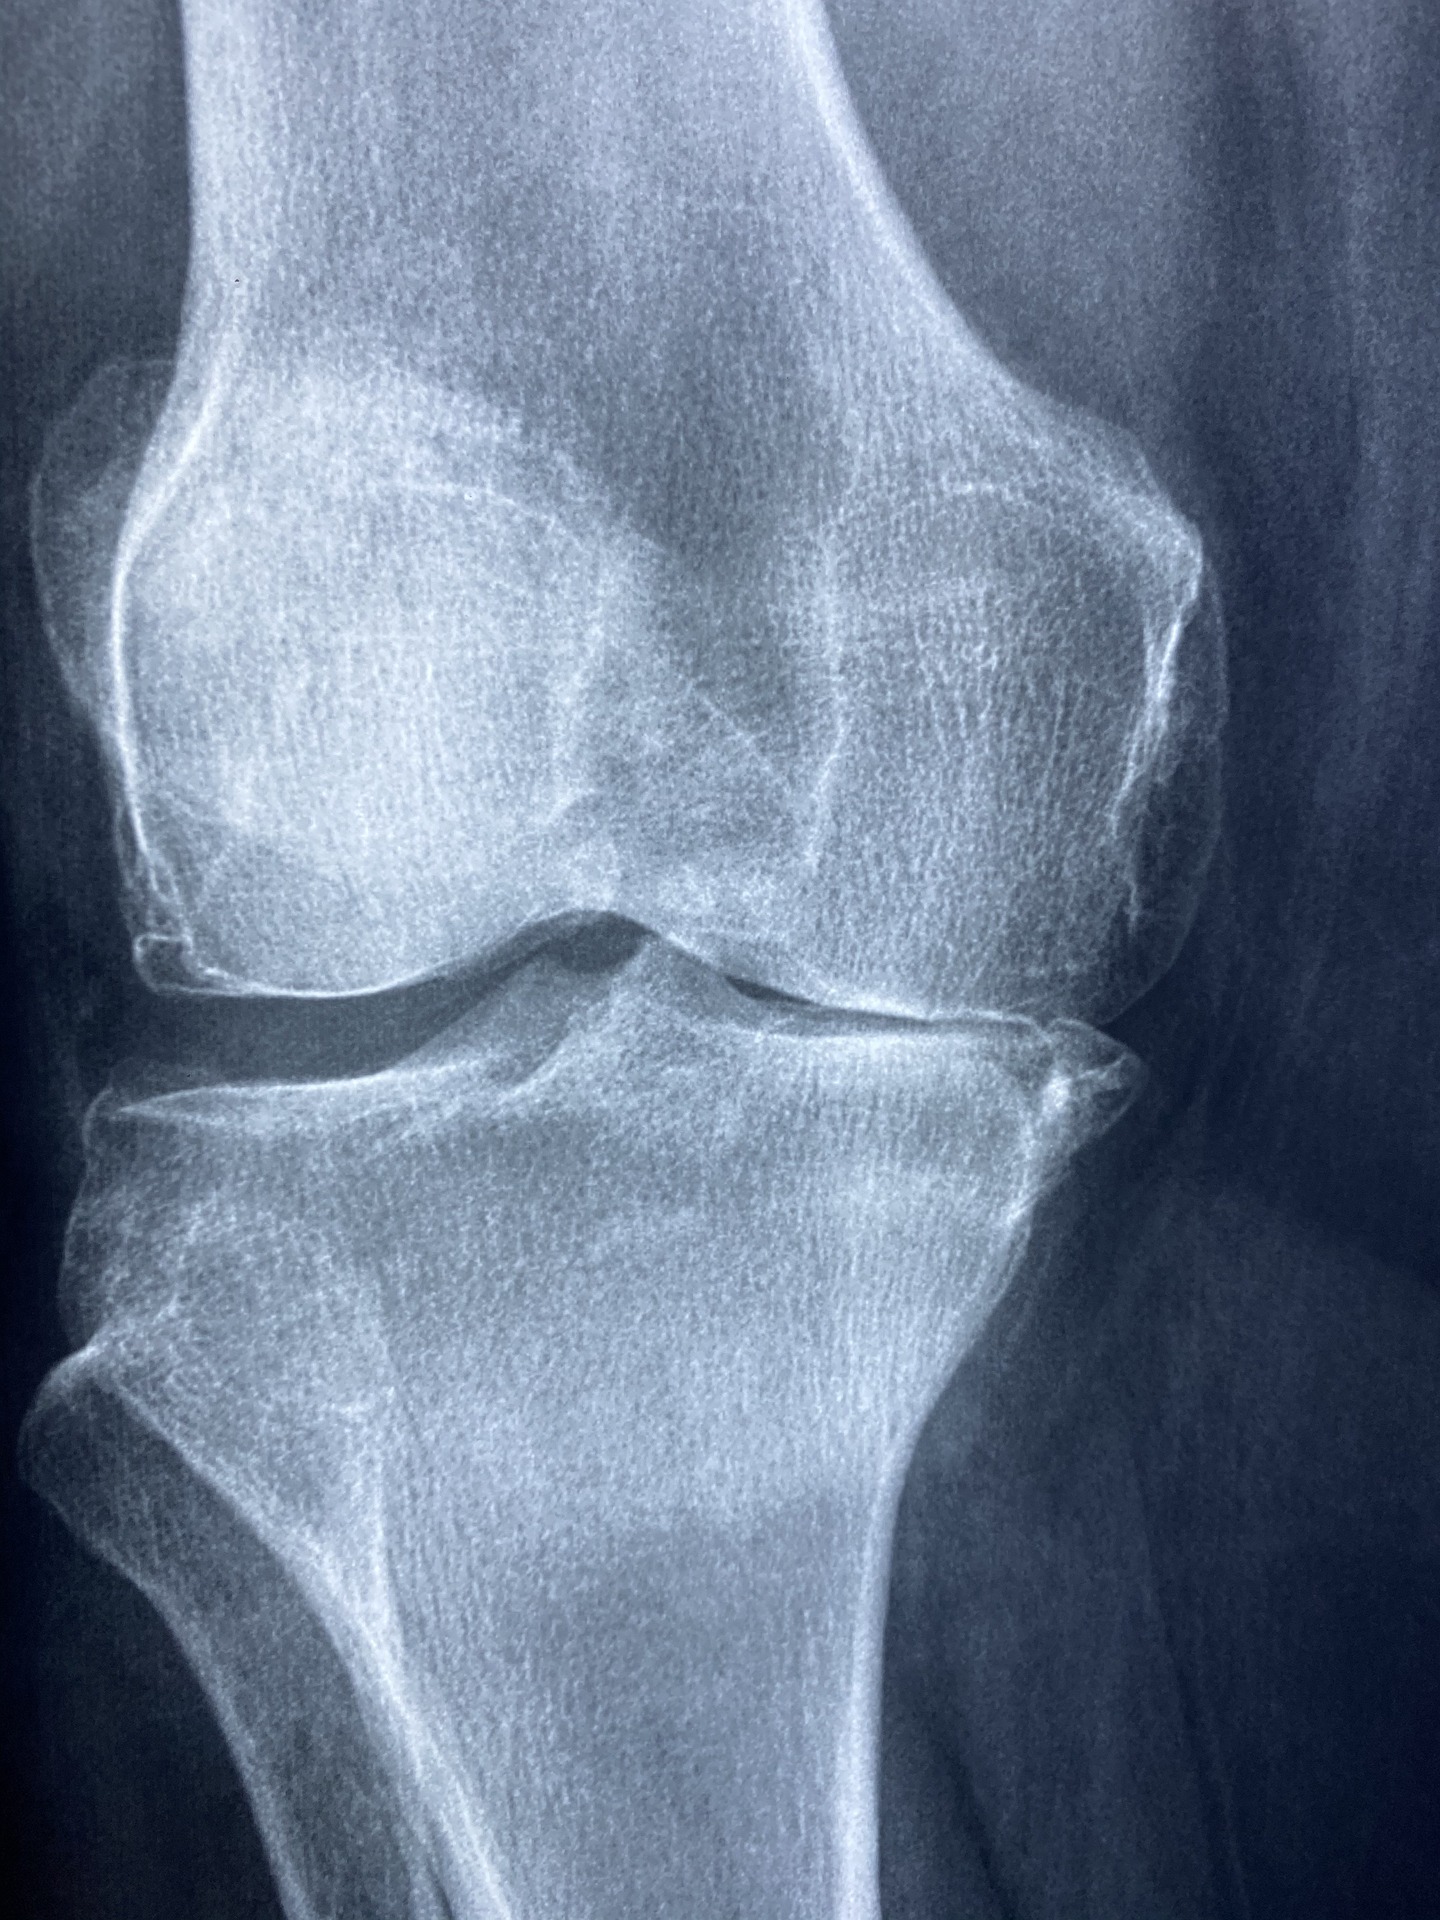

Radiology